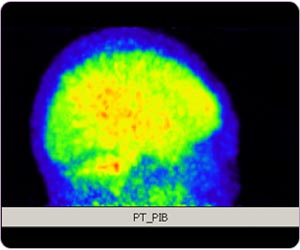

阿耳滋海默氏病 (11C標記PIB正電子掃描腦部)

由於 PIB 和 T-807 的正電子成像分別是澱粉樣蛋白和 Tau 蛋白的替代生物標誌物,NIA-AA 將 AD 的定義轉變為生物結構的決定對於未來正電子在神經病學成像的領域是一個非常合乎邏輯和重要的舉動。